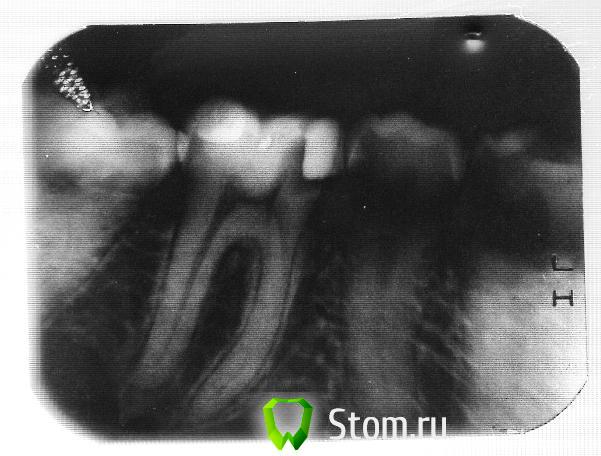

fly77 Опубликовано 18 января, 2012 Автор Поделиться Опубликовано 18 января, 2012 Посмотрите, что мне сделали((((( Это же кошмар какой то. Что теперь делать то? Каналы только до половины запломбированы, а из самих концов каналов торчат какие то иголочки. Ссылка на комментарий

Magdalena Опубликовано 18 января, 2012 Поделиться Опубликовано 18 января, 2012 (изменено) Посмотрите, что мне сделали((((( Это же кошмар какой то. Что теперь делать то? Каналы только до половины запломбированы, а из самих концов каналов торчат какие то иголочки.Добрый вечер! Зуб необходимо перелечить. Каналы должны быть хорошо обработаны и запломбированы до верхушек корней. Если оставить зуб в таком состоянии, на корнях может развиться воспаление. К большому сожалению, не всегда грамотность доктора выражается умении рассказывать и показывать в зеркало... Изменено 18 января, 2012 пользователем Magdalena Ссылка на комментарий